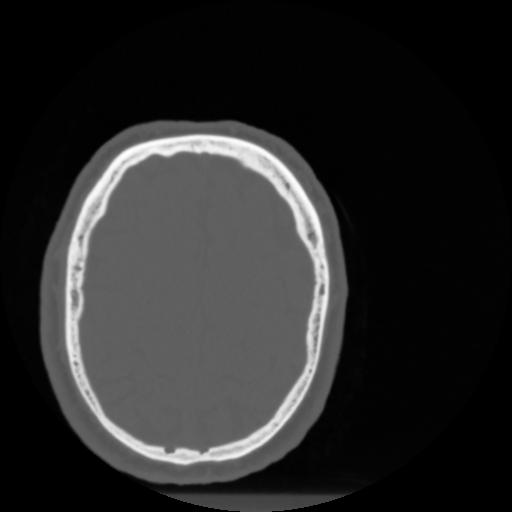

4 CEREBRO,,Vol,0.5,CEREBRO,,